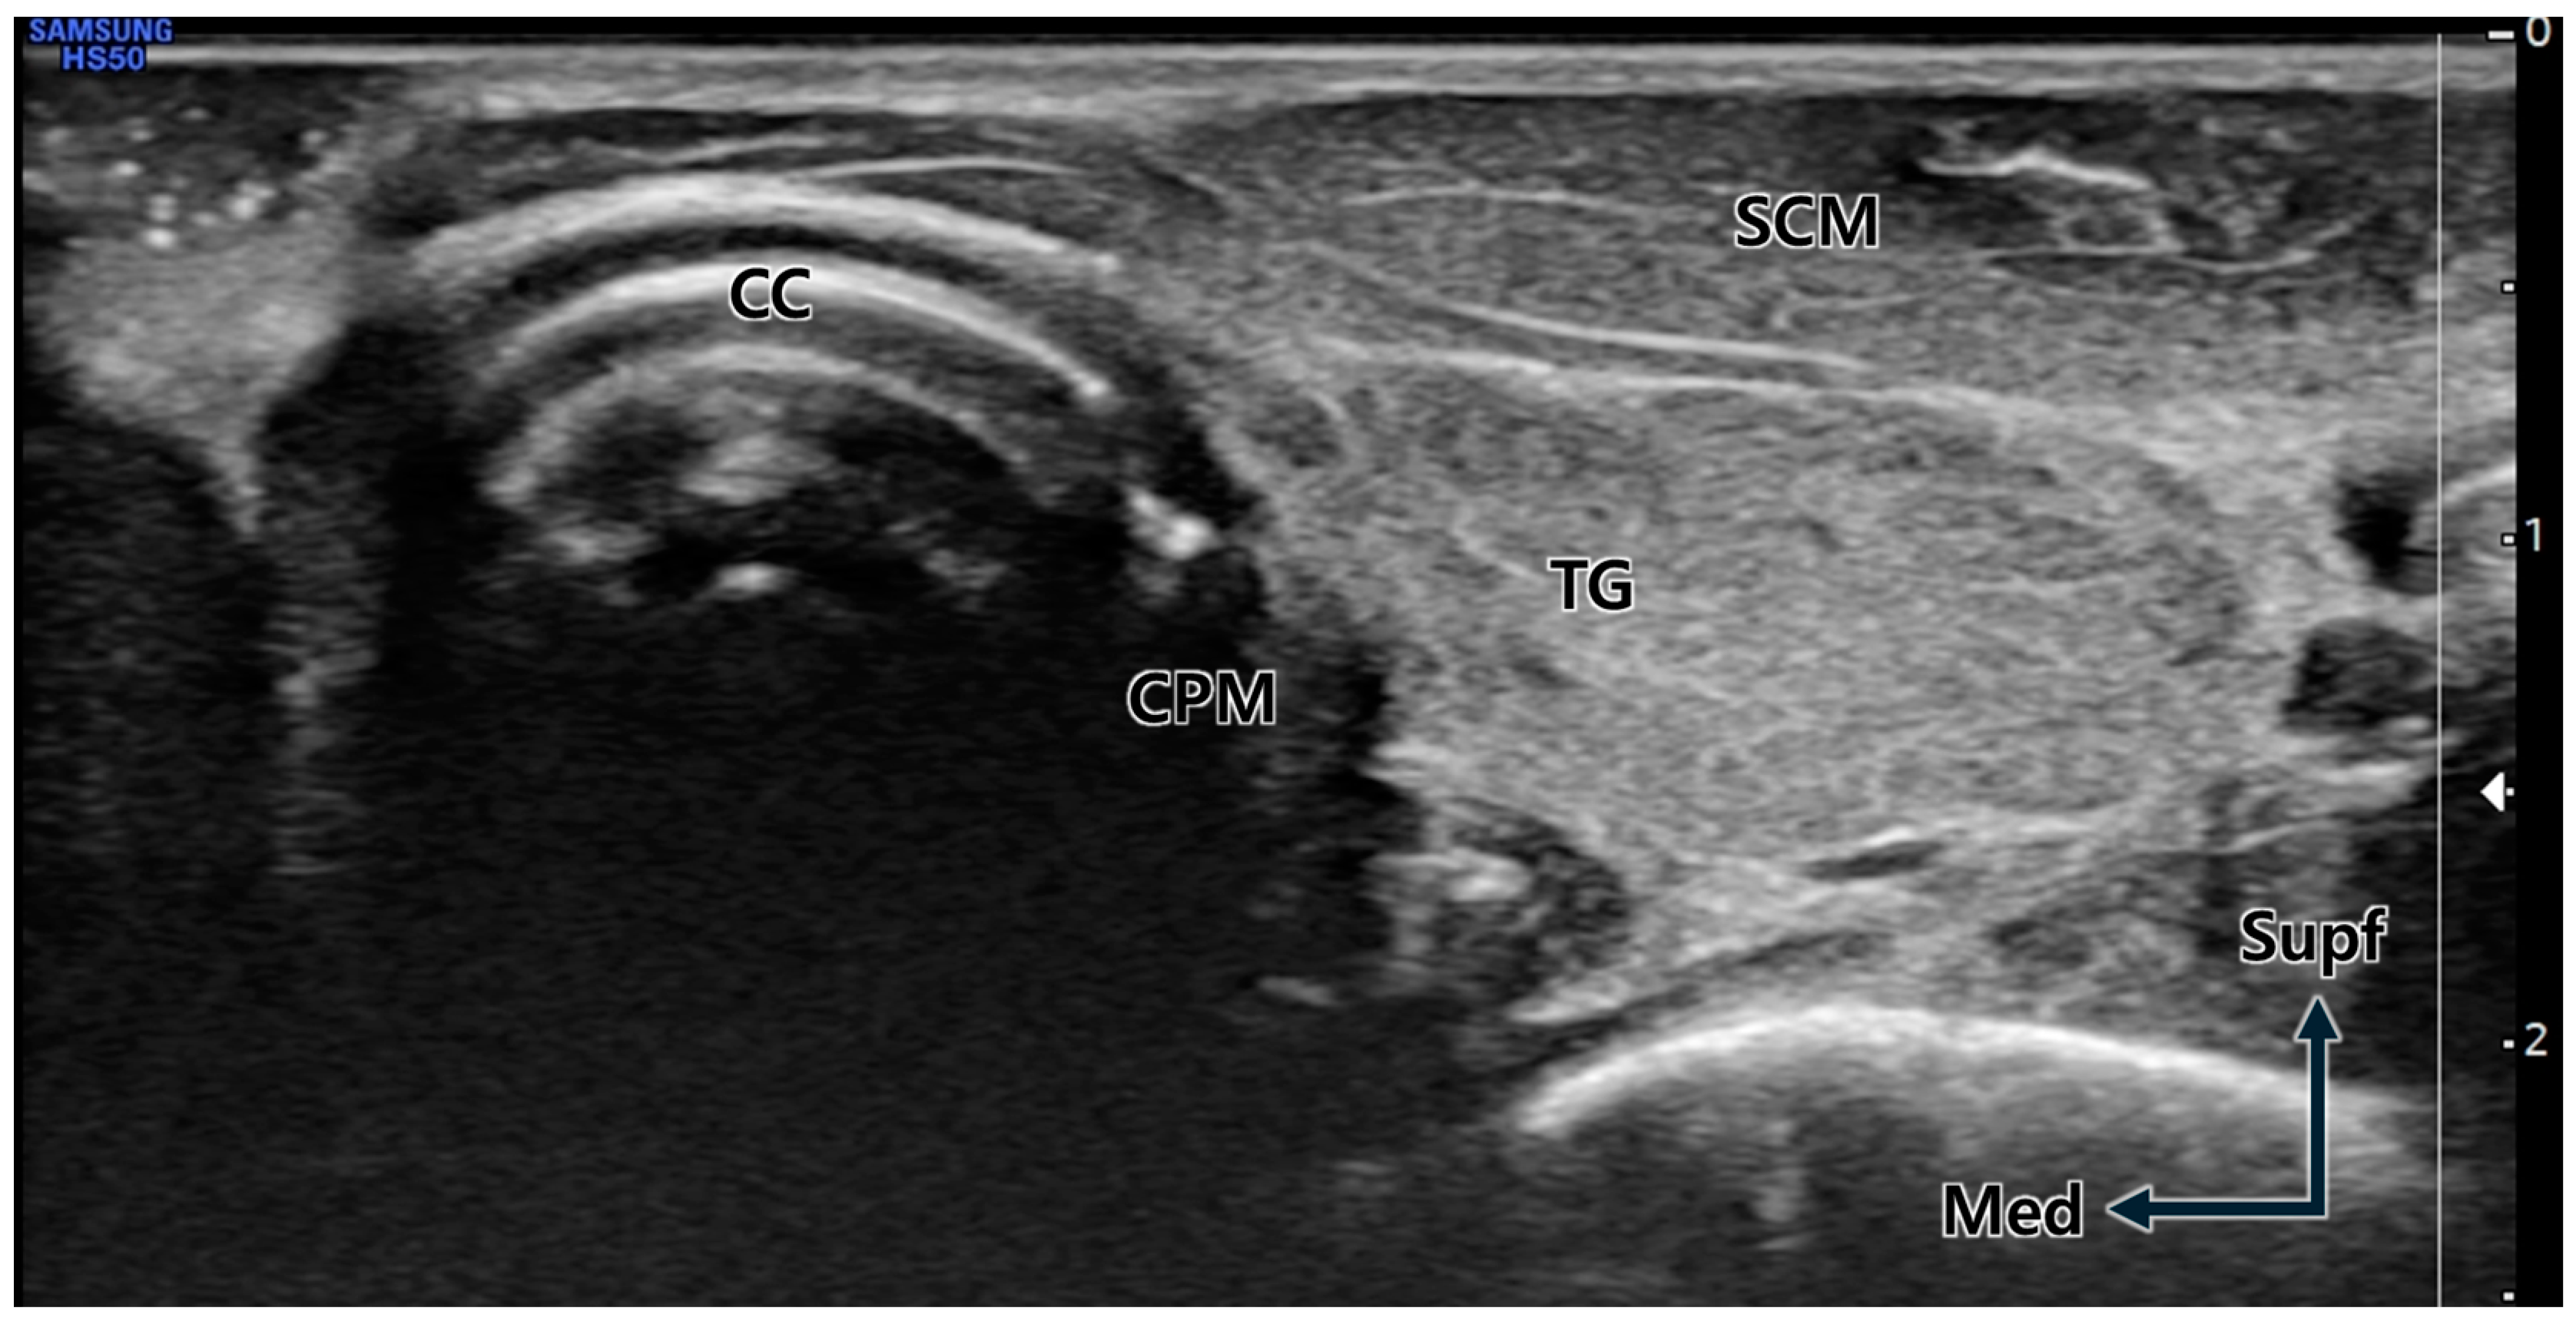

Figure 5. Transverse ultrasound image at the cricoid cartilage (CC) level. Due to the neck rotation to the lateral side, the cricopharyngeus muscle (CPM) is prominently visible immediately lateral (posterior) to the distinctly observed CC. TG; thyroid gland, SCM; sternocleidomastoid muscle, Supf; superficial, Med; medial.

The initial step for precise US-guided BNT injection into the CPM is identifying the CPM within the US view [21]. Since the left lateral areas of the CPM attached to the cricoid cartilage are superficially located close to the US probe, this area was relatively well visualized in this study. Therefore, the lateral areas of the CPM have become the optimal target point for BNT injection when using the US-guided technique. However, the CPM attached to the right side of the cricoid cartilage is not well visualized compared to that on the left side [11,21,22]. This point is thought to account for the injection failure rate being somewhat high on the right side, even though there was no statistical difference in success rate between both sides. Therefore, the cricoid cartilage is the most important landmark for advancing the injection needle into the CPM, especially in the right-side procedure. In the present study, the cricoid cartilage was used as a reliable landmark for US-guided injections to locate the CPM [8,9]. We recommend scanning the longitudinal and transverse planes to identify detailed anatomical structures surrounding the larynx, including the CPM, prior to localization. The first step is to identify the cricoid cartilage by palpation, followed by scanning the neck in the longitudinal plane to establish the transverse position of the US probe. When positioning the US probe transversely, the sternocleidomastoid muscle, thyroid gland, inferior border of the cricoid cartilage, common carotid artery, and the surface of the vertebral body served as useful landmarks to identify the CPM before injection [21]. After localizing the CPM via the US, we recommend advancing the needle along the surface of the cricoid cartilage, considering its proximal relationship with the CPM [8,9]. Utmost care should be taken during needle insertion to ensure that the thyroid gland and common carotid artery are not damaged along the needle’s path and that the needle tip does not project beyond the CPM, potentially reaching the prevertebral space and fascia (e.g., the surface of the vertebral body). As the needle is not advanced once it reaches the prevertebral fascia, it should be pulled back in order to find the needle tip in this situation.

The US-guided injection procedures were conducted using a 6 cm long 24G needle, with the target depth preliminarily determined through US imaging. For observation of the cricoid cartilage, CPM, and common carotid artery, the transducer was placed on the lateral border of the cricoid cartilage using the out-of-plane method (Figure 5).